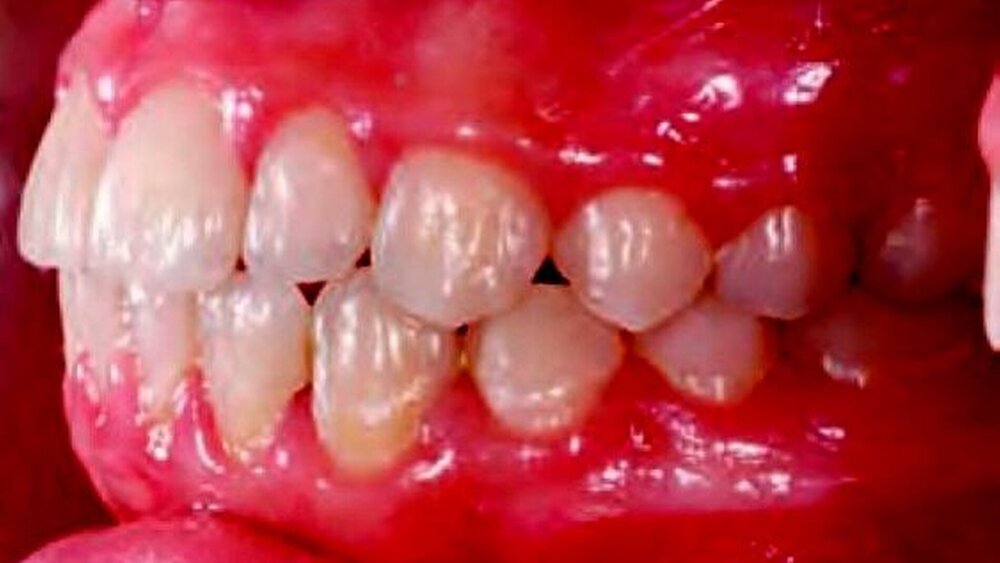

Dental bestand im Molarenbereich rechts eine Klasse-II-Verzahnung um eine Viertel-Prämolarenbreite, eine Klasse-I-Verzahnung im Molarenbereich links sowie im Eckzahnbereich rechts und links. Es waren eine deutliche transversale Enge im Oberkiefer sowie ein Kreuzbiss rechtsseitig mit Zwangsbissführung sichtbar. Frontal lag eine negative sagittale Stufe von -1 mm sowie die Tendenz zur Bissöffnung vor (Abbildungen 1e bis 1g). Das Orthopantomogramm (OPG) zeigte eine Rotation des Zahnes 12 und eine Tendenz zur Retention des Zahnes 13 (Abbildung 1d). Die Auswertung des seitlichen Fernröntgenbildes (FRS) ergab eine skelettale Klasse III bei retrognathem Ober- und orthognathem Unterkiefer bei neutralem Wachstumsmuster mit vertikaler Tendenz.

Abbildung 1 zeigt die typische Kreuzbisssymptomatik, eine Laterognathie zur Kreuzbissseite. Bei 80 Prozent der Patienten mit einseitigem Kreuzbiss entwickelt sich eine funktionelle Unterkieferabweichung [Kurol et al., 1992]. Hieraus kann eine asymmetrische Kiefergelenkkopfposition entstehen, wobei der kreuzbissseitige Kondylus nach kranial und dorsal (Kompression) und der kontralaterale Kondylus nach anterior und kaudal (Distraktion) bewegt wird [Lippold et al., 2008]. Der einseitige Kreuzbiss verbunden mit einem lateralen Zwangsbiss fördert eine adaptive Umformung der Gelenkköpfchen und ein asymmetrisches Wachstum des Unterkiefers.